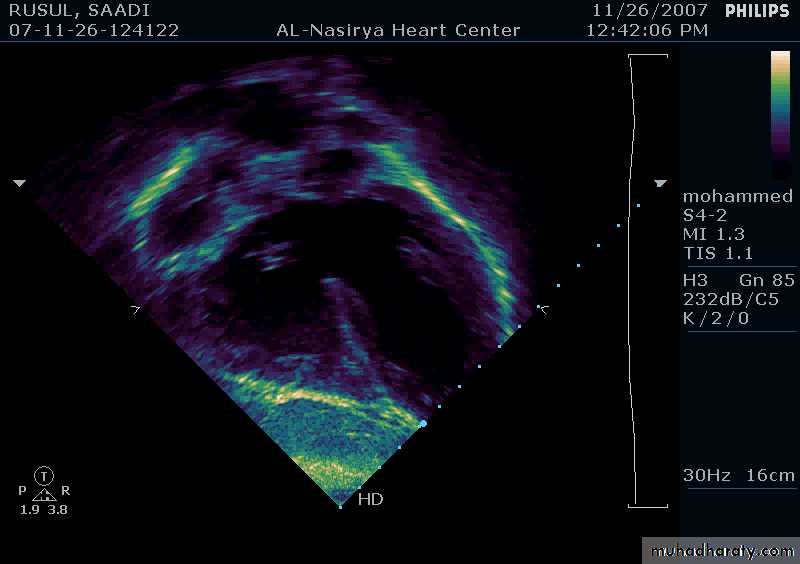

33Echocardiography & TEE

Shows the size of the defectThe direction of blood flow

The pulmonary artery pressure34

Ostium Secundum ASD

35

36